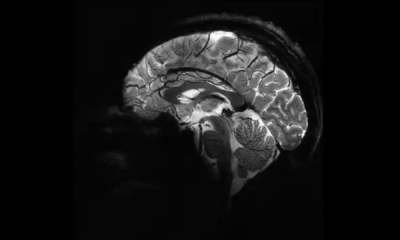

O cérebro dos homens pode “encolher” em até 70% ao longo do dia, entre 7h e 20h, antes de se “reiniciar”, segundo um novo estudo. Esse...